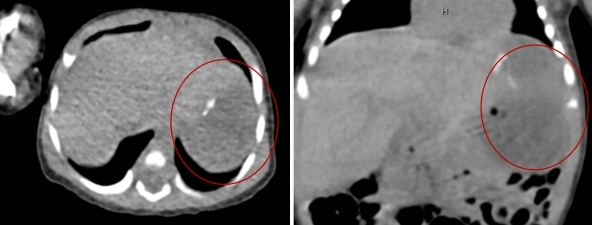

接诊当天,新生儿科迅速安排宝宝入住了病房,同时组织儿童普外/胸外/血管瘤外科、麻醉科等多学科团队进行术前会诊,对宝宝的情况做周密的评估。入院时宝宝身长52cm,体重3.0Kg,肚子仅“成人手掌”一般大小!术前检查显示,患儿肝脏左外叶有一大小约51x48x35mm的包块,考虑肝脏左外叶肿瘤可能性大,有手术干预指征!经讨论,决定采用“腹腔镜下肝脏肿瘤切除术”的治疗方案。

腹部CT可见肝脏左外叶包块--红圈标注